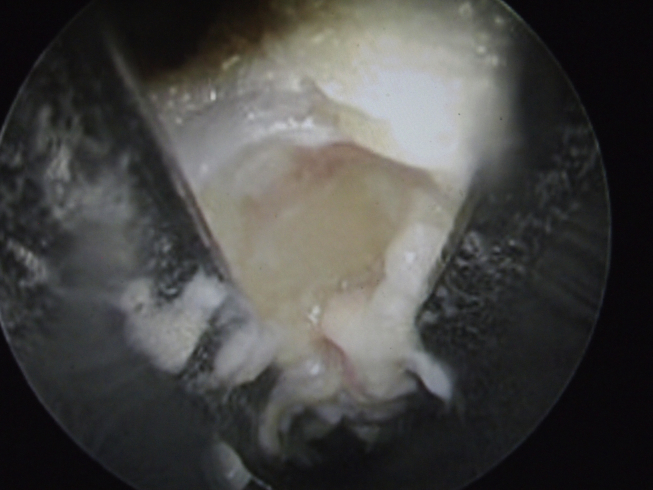

Fig. 6.

The lumbrical tendon was left side of the TIML.